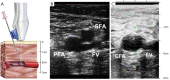

Echocardiographic guidance has an important role in percutaneous cardiovascular procedures and vascular access. The advantages include real time imaging, portability, and availability, which make it an effective imaging modality. This article will review the role of echocardiographic guidance for diagnostic and therapeutic percutaneous procedures, specifically, transvenous and transarterial access, pericardiocentesis, endomyocardial biopsy, transcatheter pulmonary valve replacement, pulmonary valve repair, transcatheter aortic valve implantation, and percutaneous mitral valve repair. We will address the ways in which echocardiographic guidance provides these procedures with detailed information on anatomy, adjacent structures, and intraprocedural instrument position, thus resulting in improvement in procedural efficacy, safety and patient outcomes.